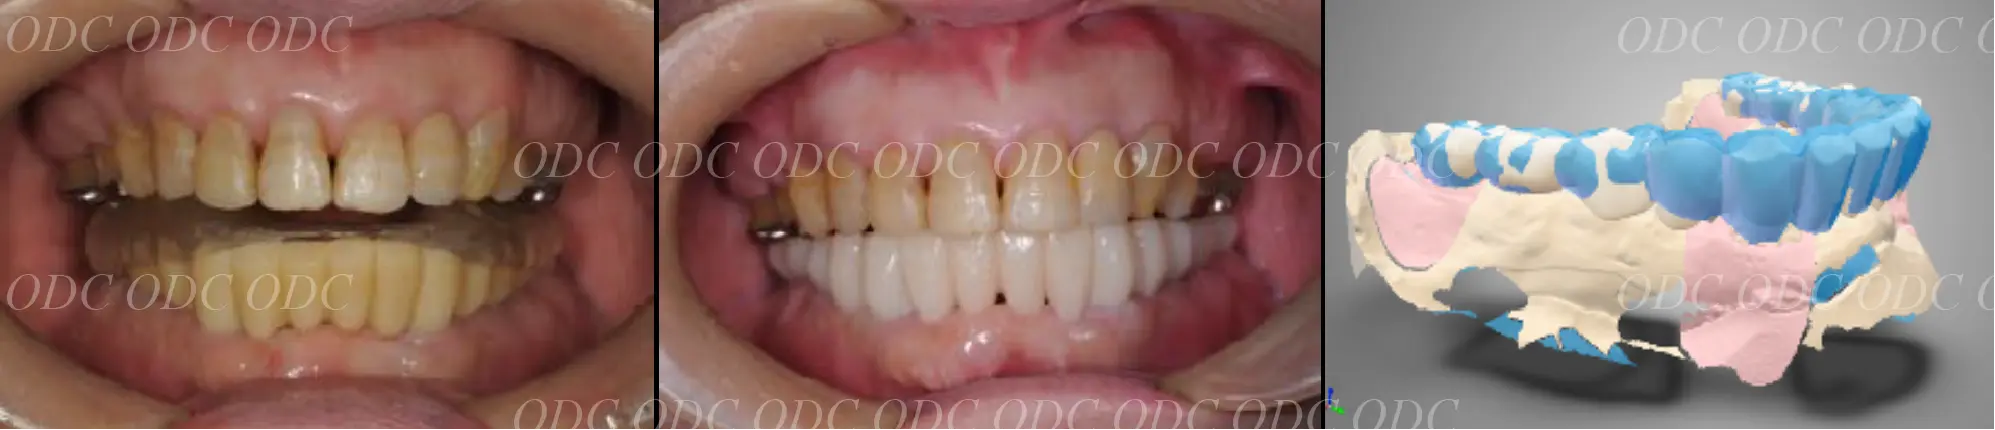

前歯がもともと4本、生えてこなかった症例。

コンピューターで計画を行い、上部構造に関してもコンピューターにてデザイン。

最終物が装着されるまでに第1のプロビジョナルレストレーション(上段)と第2のプロビジョナルレストレーションを装着。

最終の補綴物が装着された、口腔内写真とレントゲン写真。